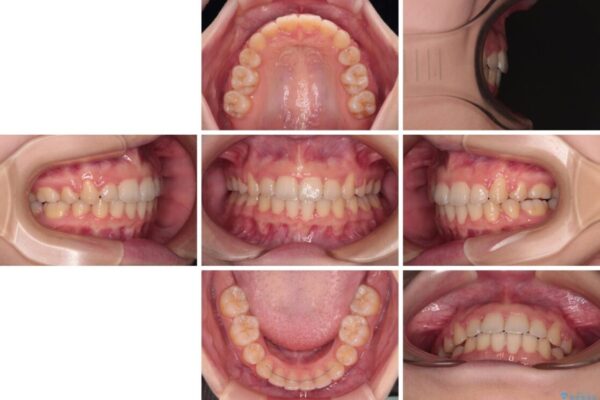

治療前

• 【モニター】口が閉じられない ワイヤー装置での抜歯矯正 治療前画像